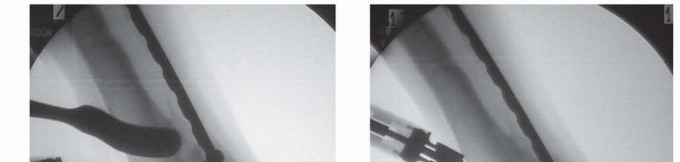

## The plate is then removed and an oscillating saw is used to create an osteotomy perpendicular to the long axis of the tibia (TECH FIG 5A).

TECH FIG 5 • A. Transverse osteotomy through distal tibia at metaphyseal-diaphyseal junction. B. Locking plate secured to the proximal fragment prior to derotation of the distal tibia. C. Image from distal of the thigh-foot angle showing correction of external tibial torsion prior to securing the distal fragment. D. Locking plate secured to distal tibia using combination of locking and nonlocking screws after correction of external tibial torsion.

## The plate is then placed once again along the tibia and secured to the tibial shaft (TECH FIG 5B). The distal tibia is then derotated to a position where the thigh-foot angle is neutral (TECH FIG 5C).

## The distal fragment is then secured to the plate using screws. If a locking plate has been selected to stabilize the osteotomy, locking screws should be used to secure the distal fragment to the plate (TECH FIG 5D).